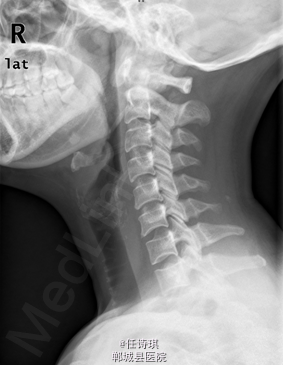

女,46岁8月,因“颈部不适3年,右上肢软弱疼痛伴双下肢胀痛1年”入院。3年前无明显诱因出现颈部不适,以局部胀痛为主,劳累后加重休息后可缓解,不伴上肢放射痛。遂未予特殊处理。1年前出现右上肢酸麻肿痛,以肘关节疼痛和手部皮肤麻木为主,行走约10分钟后自觉双小腿后侧胀痛,休息后可缓解。在当地医院诊断为“网球肘、颈椎病”予以对症治疗,但上述症状无明显改善。行MRI、CT等检查,诊断为“C2椎管内肿瘤”,未予特殊治疗。为求进一步诊断今日由门诊以“C2椎管内占位,性质?”收入院

专科查体:视:脊柱无明显畸形。触:颈胸部各棘突无明显压、叩痛。四肢肌张力正常,右手皮肤触觉减退。动量:右侧上肢肌力IV级,左侧肢体V级。右侧上肢腱反射活跃,双侧膝腱反射活跃,跟腱反射正常引出。Hoffman征阳性,Babinski征未引出。外院MRI示:C2椎管内脊髓背侧占位病变,脊膜瘤可能。T2椎体内异常信号,多为血管瘤。。

初步诊断:1、颈2节段椎管内占位伴不全四肢瘫(Frankel D):脊膜瘤?黄韧带骨化? 2、胸2椎血管瘤 处理:全麻下行经后路颈2全椎板切除、椎管探查减压、椎管内占位切除活检术,